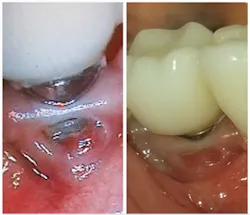

We educate our patients on brushing and flossing and hope they do this on a regular basis, but even when they do brush and floss, it is still only mechanical. IfStudies have concluded that therapeutic substances in certain products are able to reduce the viability of pathogens in biofilm.6-10 Activated chlorine dioxide is such a substance. It has the ability to kill bacteria, viruses, and fungi, break up biofilm, and reduce volatile sulfur compounds. This active ingredient can be safely used daily for both implant and regular hygiene (figure 1). One such product that contains these ingredients is OraCare’s Reassure system. This product has a gel to help immediately during surgery, and a rinse to help the patient at home.